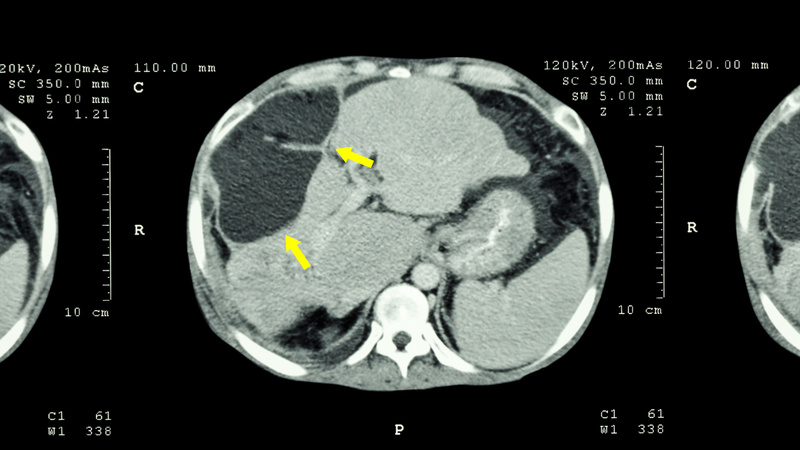

日本では医療者の友人から得た情報や、銀行からの勧めなどを比較検討し、国立がんセンターでフォローを受けることに決めました。国立がんセンターは、大腸がんの転移が起こりやすい肝臓と肺、どちらの治療成績もよい施設であったためです。3か月ごとに同病院で検査を受け、1986年夏、恐れていた肝臓への転移がついに確認されました。